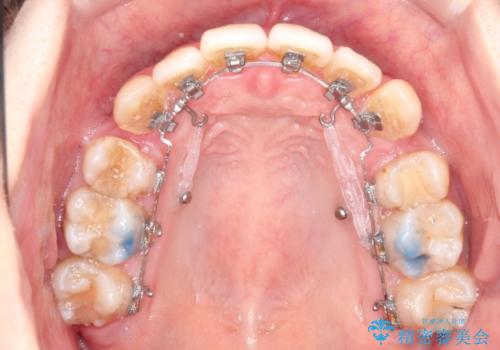

- ハーフリンガル

目立たないワイヤー矯正を希望されたので、上下左右のはを1本ずつ抜歯して、ハーフリンガル(上顎だけ裏側)にて矯正をすることにしました。

裏側装置の場合、歯磨きが難しいのと、慣れるまでは話しにくさや、違和感があります。

慣れてからは、とくに不自由さは感じない方が多いです。